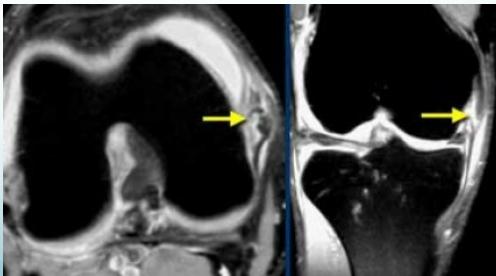

MRI

- Best for assessing soft tissue damage